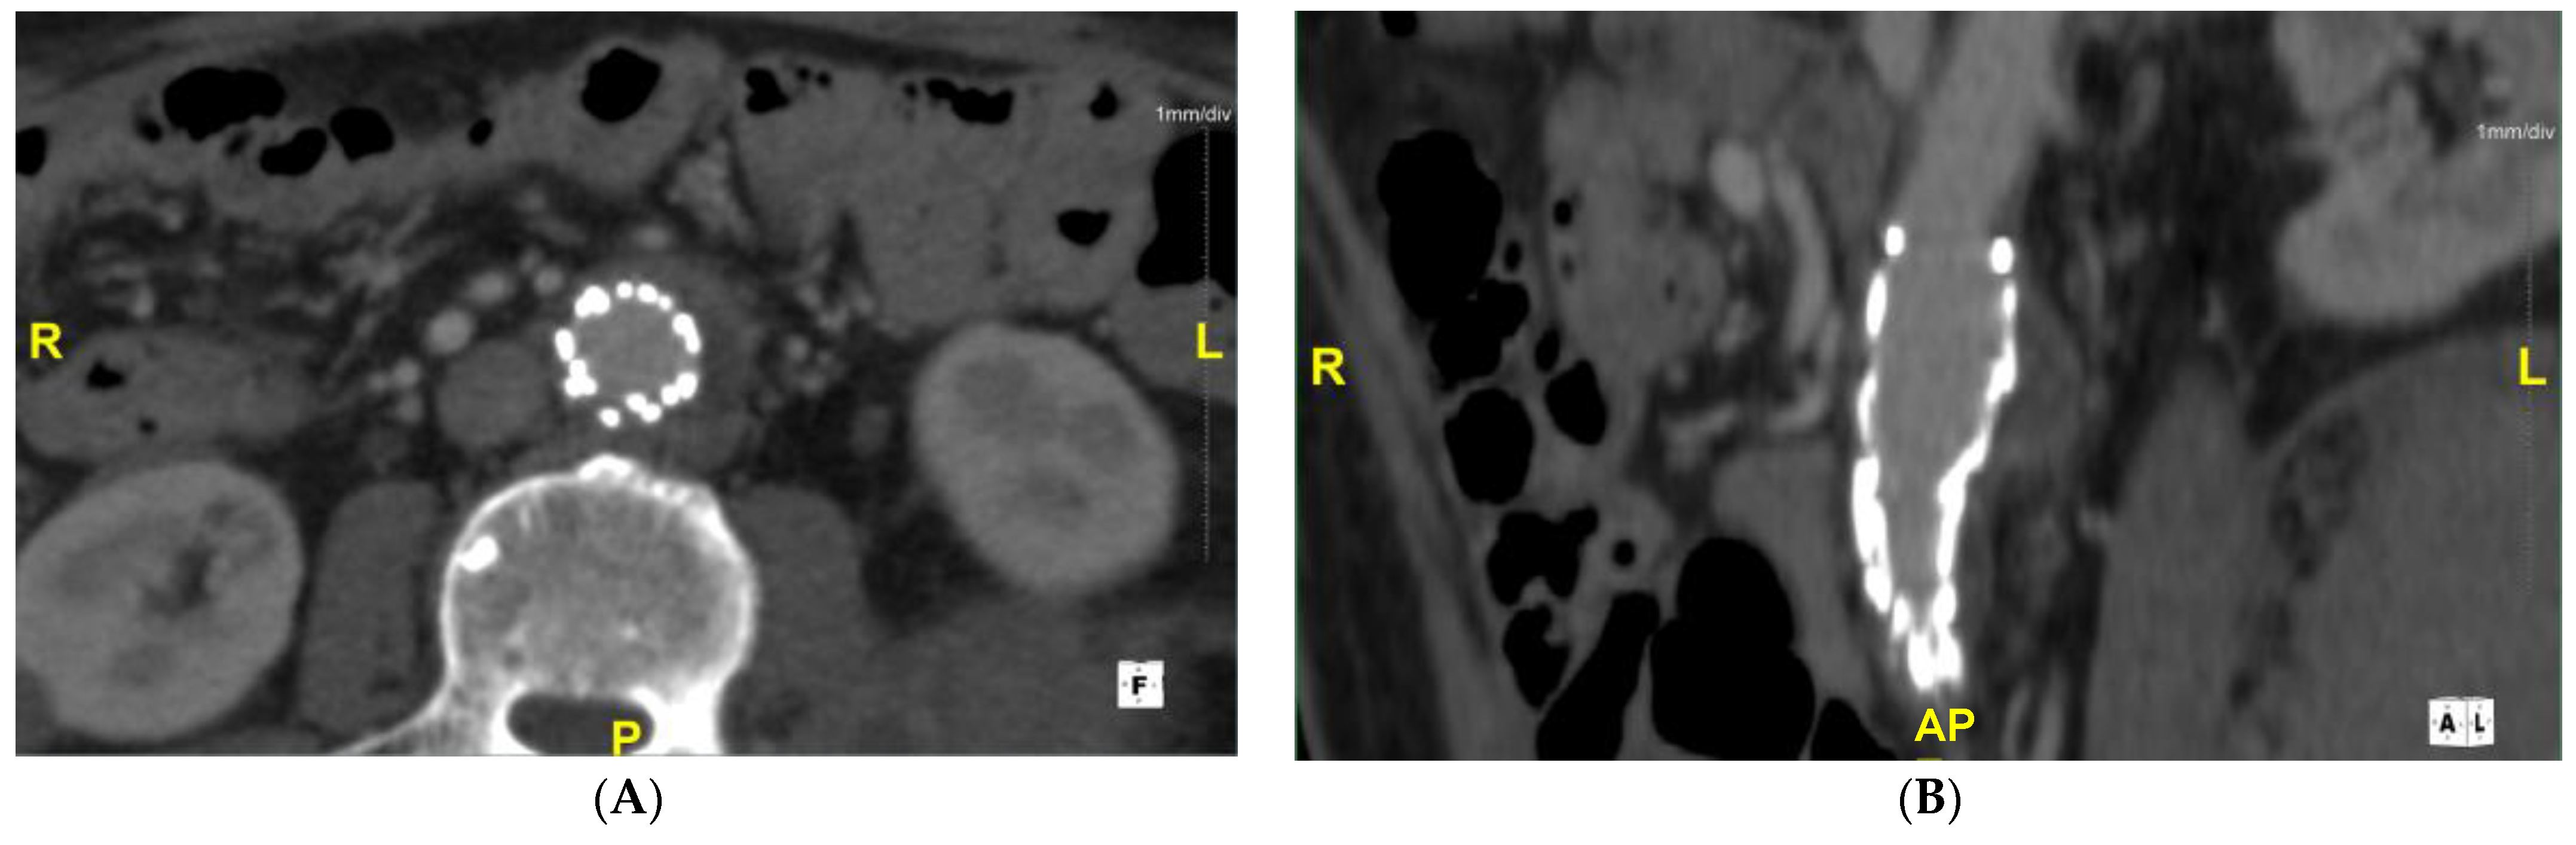

2. Case Report